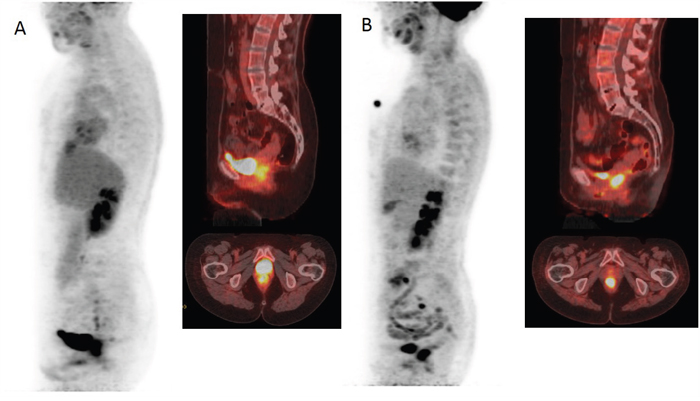

Figure 1a shows ROC analysis for ΔSIS and ΔSUVmax in discriminating responders from non responders. The optimal cut-off for ΔSIS was a reduction of 6.0% yielding 92.7% of sensitivity and 80.0% of specificity to identify responder patients. Instead, the optimal cut-off of 59.7% for ΔSUVmax showed lower accuracy in identifying responder patients than ΔSIS, with a sensitivity of 67.3% and a specificity of 75.0%. 55 patients were classified as responders by ΔSIS, including 51 true positives, while 41 patients were classified as responders by ΔSUVmax, including 37 true positives. The combination of ΔSIS and ΔSUVmax did not increase predictive ability, classifying 43 patients as responders, of whom only 36 were true pathological responders. Figure 1b shows ROC analysis for ΔSIS and ΔSUVmax in discrimination pathological complete response (TRG1) by incomplete response (TRG 2-4). The optimal cut-off for ΔSIS was a reduction of 30.3% (93.3% of sensitivity and 68.9% of specificity) while the optimal cut-off of 43.9% for ΔSUVmax showed lower accuracy (sensitivity of 80.0% and specificity of 31.1%). Statistically significant differences between ΔSIS and ΔSUVmax, in terms of both sensitivity and specificity, were assessed using the McNemar test (p value <0.05), for both analysis. The presurgical PET/CT analysis demonstrated a low level of correlation between median ΔSUVmax value with pT and TRG findings (Spearman's rank correlation coefficient = -0.2 and -0.3, respectively), while a good level of correlation was observed between median ΔSIS value and pT and between median ΔSIS value and TRG (Spearman's rank correlation coefficient = -0.6 and -0.7, respectively). Table 3 shows the performance of ΔSIS and ΔSUV analysis to identify responder from non-responder patients and complete by incomplete pathological response. Figures 2 and 3 show DCE-MRI and 18F-FDG PET/CT images respectively, for a responder patient (TRG = 1). Figures 4 and 5 respectively show DCE-MRI and 18F-FDG PET/CT images, for another responder patient (TRG = 2)recognized only to ΔSIS analysis.

Figure 5: 18F-FDG PET/CT images before A and after B treatment demonstrating a minimal reduction of glucose metabolism with ΔSUVmax of 6.07% classifying the patient as non responder.